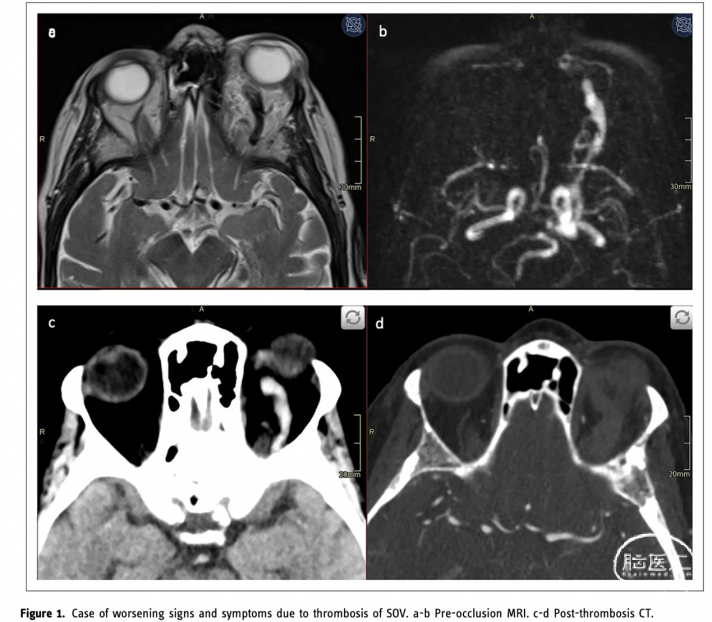

临床症状加重的患者分析显示临床恶化可能与后续血管成像中造影剂流动缓慢或停滞有关(表3)。这在自发闭塞的CSDAVF和接受治疗的患者中都可以观察到。病例18是一名76岁的患者,表现为严重的眼球突出、水肿、结膜充血、眼外肌活动受限、眼部疼痛和眼压升高,在MRI和动态MRA上被诊断为CSDAVF(图第1a和b段)。术后8周眼球突出恶化,进行CTA扫描显示CSDAVF一侧的眼上静脉和海绵窦完全血栓形成(图1c和d),行密切观察,症状和体征在2天内好转。

图1. 眼上静脉闭塞导致症状恶化加重的典型病例